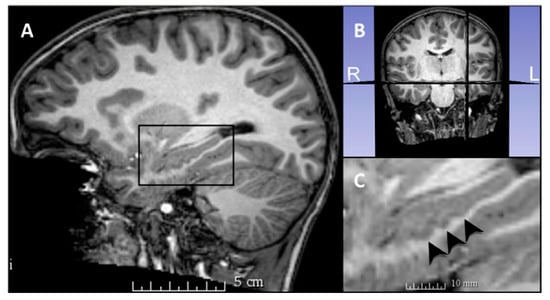

Hippocampal dentation, present in the CA1/subiculum of the human hippocampus, was assessed in this study by counting the number of hippocampal dentes for the left and right hippocampus of each participant individually (Figure 1, Figure 2 and Figure 3). Hippocampal dentation was visualized in the sagittal plane, using all available sagittal slices to determine the total number of dentes for each hippocampus. Hippocampal dentation was described previously in adults using ultra high-resolution structural neuroimaging (HR-MICRA technique with 0.5 × 0.5 × 0.75 mm3 resolution) []. While a previous study described hippocampal dentation in terms of both quantity and prominence, in this study, dentation was measured by quantity only, adapted due to the reduced visibility of dentation and the SRLM layer (stratum radiatum, lacunosum, and moleculare) in this scan resolution. See Beattie and colleagues (2017) for more detailed methodology on the previous study. In the current study, right and left hippocampal dentes were counted for all participants by a researcher trained in hippocampal anatomy (J.F.B.). The main analyses were conducted using these results. Approximately 25% of scans (n = 24) were counted by two additional trained researchers (T.A.C. and R.Q.J.) to assess inter-rater reliability. All raters were blinded to participant variables, including age, while counting dentation.

Figure 2. (A) Sagittal view of the left hippocampus of a 9-month-old participant. The black box highlights the location of the hippocampus in this view. (B) Coronal view indicating the lateral placement of the sagittal plane seen in (A,C). (C) A more detailed view of the left hippocampus for this participant, with no visible dentes and the smooth contour of the inferior aspect of the hippocampus traced.